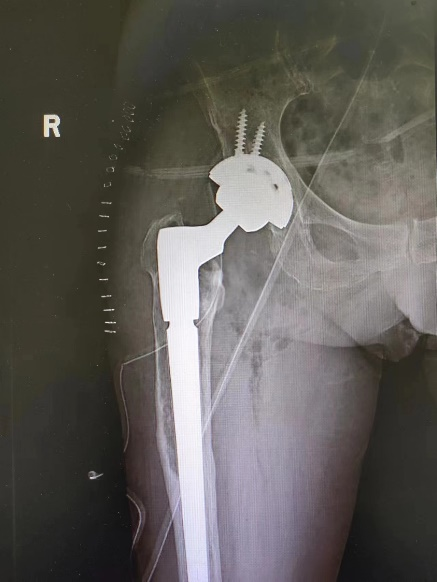

骨科副主任王建伟门诊查体并进行髋 DR 检查发现,患者右侧人工髋关节假体周围骨溶解严重,假体下沉松动。于是骨科团队考虑患者疼痛为人工髋关节置换术后假体松动所致,要想彻底治愈只能做翻修手术。

3 月 8 日,由骨科副主任王建伟主任医师主刀,李延明副主任医师、蔡文龙主治医师、杨志军住院总医师为助手,髋关节翻修手术历时 3 小时按照术前计划顺利完成。术后拍患肢 X 光片提示翻修假体型号、位置良好,完全纠正了术前患肢的短缩畸形。